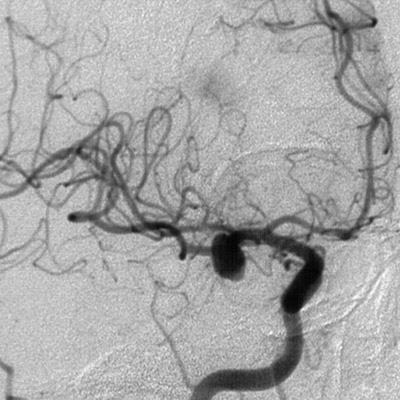

In cerebral angiogram lateral view above can be seen a berry aneurysm involving the middle cerebral artery of the circle of Willis at the base of the brain.